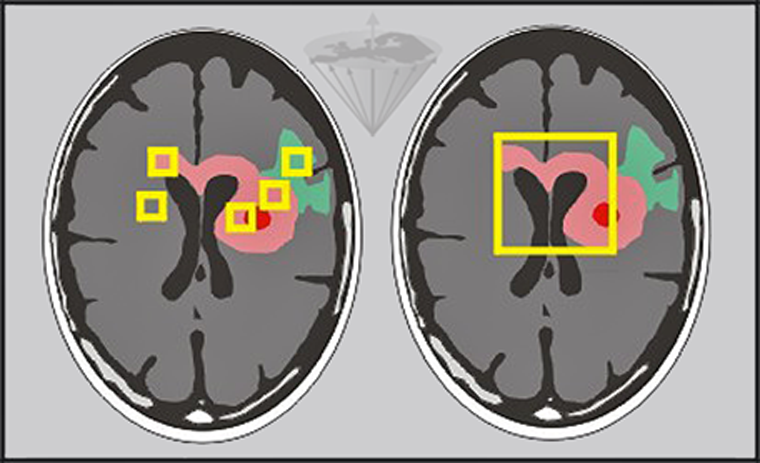

Otras posibles fuentes de error son la desviación estándar de los ajustes, los artefactos y las variaciones en la selección de elementos del volumen hechas por los operarios (Figura 04-21).

Figura 04-21:

Se pueden hacer mediciones de los tiempos de relajación in vivo ya sea pixel por pixel o por regiones de interés de diferente tamaño.

Izquierda: Pequeñas regiones de interés en edema (verde), tumor (rosado) y necrosis (rojo) y otras patologías.

Derecha: Una región más grande que cubre las principales partes del tumor.